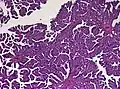

The tumor is neuroectodermal in origin and similar in structure to a normal choroid plexus. They may be created by epithelial cells of the choroid plexus. Papillary fronds lined by bland columnar epithelium are visible under the microscope. Normal absences include mitotic activity, nuclear pleomorphism, and necrosis.[10] Tumors have positive immunohistochemistry for cytokeratin, vimentin, podoplanin, and S-100.[11] Up to 20% of choroid plexus papilloma patients may test positive for glial fibrillary acidic protein (GFAP).[12] Studies have found that fourth ventricle cancers express more S100 than lateral ventricle tumors, and older patients (over 20 years) express more GFAP and transthyretin than younger patients.[13] Some individuals with choroid plexus papilloma have germline TP53 gene mutations, according to genetic analyses.[14] These cancers rarely exhibit nuclear p53 protein positivity. Aicardi syndrome, hypomelanosis of Ito, and 9p duplication are syndromic correlations of choroid plexus papilloma.

Plexuspapillom Detail -